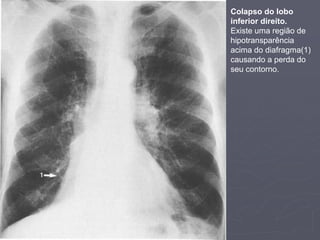

Colapso do lobo

inferior direito.

Existe uma região de

hipotransparência

acima do diafragma(1)

causando a perda do

seu contorno.